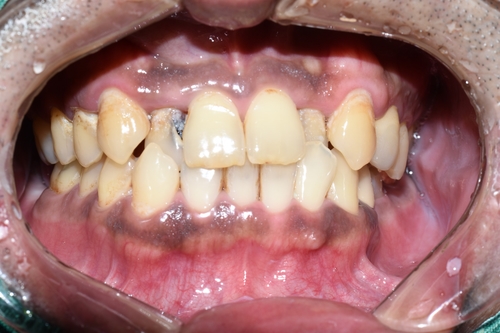

앞니가 많이 썩은 환자분으로,

보이는 앞니의 충치 뿐만 아니라 보이지 않는 입천장 쪽의 충치, 치아 사이 속의 충치도 있었습니다.

앞니 충치 치료전

앞니 4개 모두 충치치료가 필요한 상태입니다.